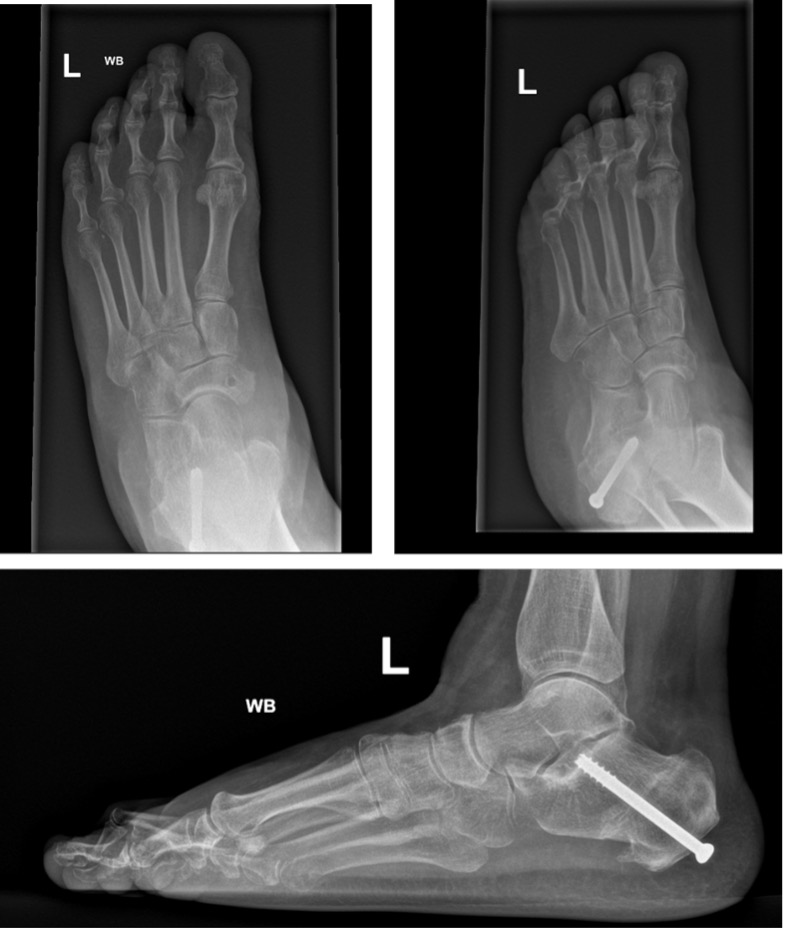

Stage IIA: Medialising calcaneal osteotomy + FDL transfer (Fig 9,10)

Figure 10b: Post-op standing radiographs (of Figure 7) showing restored talar head coverage and Meary’s angle